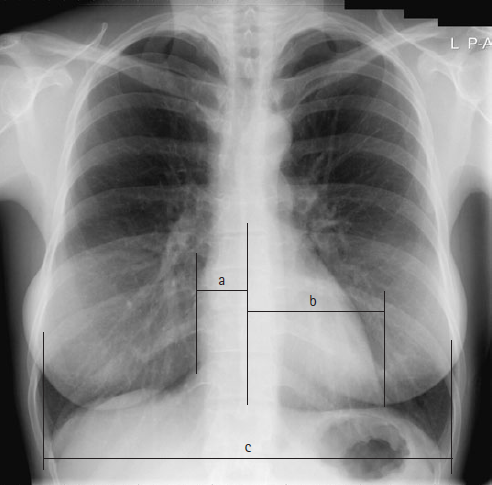

Heart की साइज Chest PA radiograph द्वारा CTR (Cardio-thoracic ratio) की सहायता से मापी जाती है |  यह heart की maximum transverse diameter तथा costo-phrenic angle के ऊपर चेस्ट की maximum width का अनुपात होता है | ये मापन रिब्स के आंतरिक किनारे से किया जाता है |

Cardio-thoracic ratio (CTR) = (a+b) / c

chest radiograph showing cardiomegaly measurements

यहाँ

a= mid line से हार्ट के राइट बॉर्डर की दुरी |

b= mid line से हार्ट के लेफ्ट बॉर्डर की दुरी |

c= costo-phrenic angle के ऊपर चेस्ट की अधिकतम चौड़ाई |

Adult में नार्मल CTR 0.5 होता है |

0.5 से अधिक CTR, cardiomegaly को बताता है |

Ex. यदि a= 2.5 cm, b= 10 cm तथा c= 29 cm हो तो CTR क्या होगा ?

CTR = (2.5+10) / 29

= 0.43